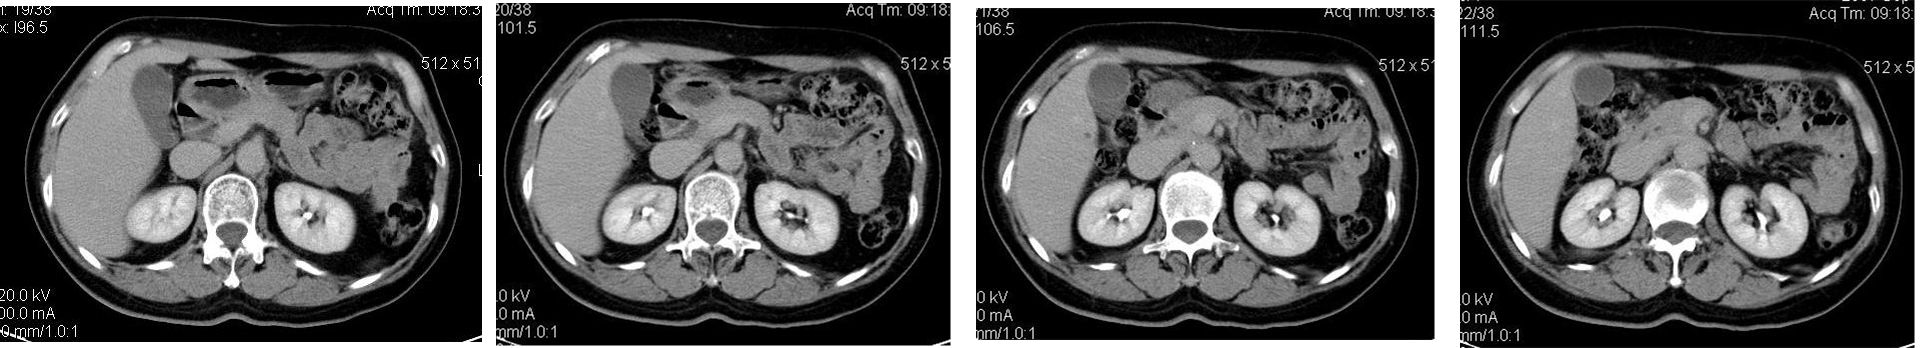

患者,女,65岁,住院准备甲状腺腺瘤用术,术前常规发现肝脏占位,ct增强扫描。

符合快进快出表现,还是考虑:肝左叶内侧段肝癌.

造影剂快进快出,考虑:肝左叶内侧段肝癌.

肝左叶内侧段肝癌,肝右叶可见小结节灶,并见强化,考虑转移.

肝左叶内侧段低密度灶,增强明显快进快出表现,考虑:肝癌。

学习了,这可能是脂肪含量少的血管平滑肌脂肪瘤,因血管丰富所以动脉期密度升高明显,但该患无肝硬化表现,所以,诊断肝癌,依据不足.谢谢上传.对今后工作是一个提醒.